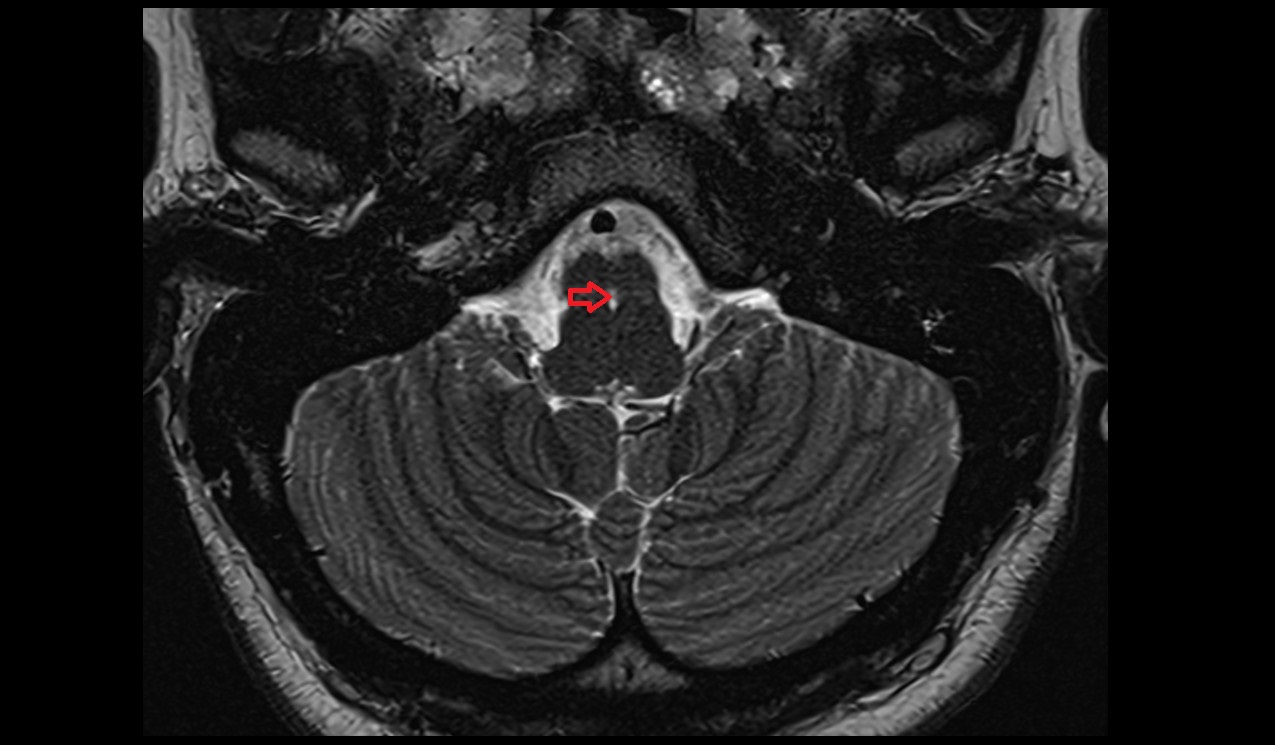

- Meckel’s cave (Trigeminal cave)